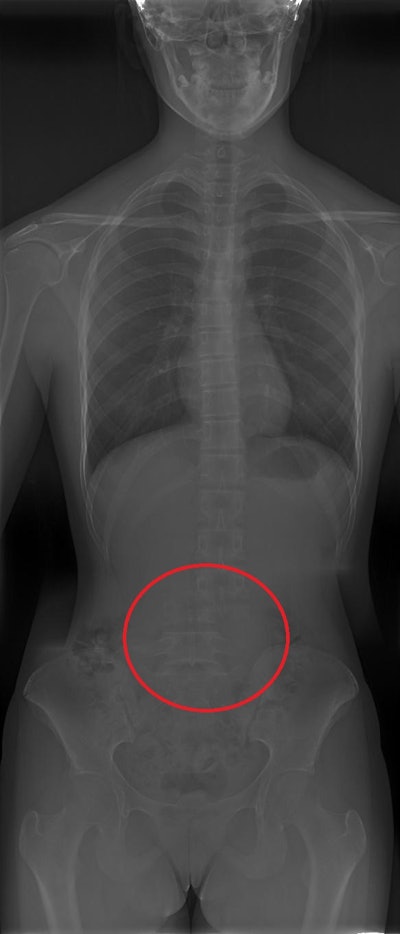

Reconstruction artifact in which a shift in part of the spine is shown. All figures courtesy of P. Garcia Castañon, S. Honorato Hernandez, C. Prieto Martin et al and ESR EPOS database.

A more subtle stitching artefact is shown, where two vertebrae seem to be united.